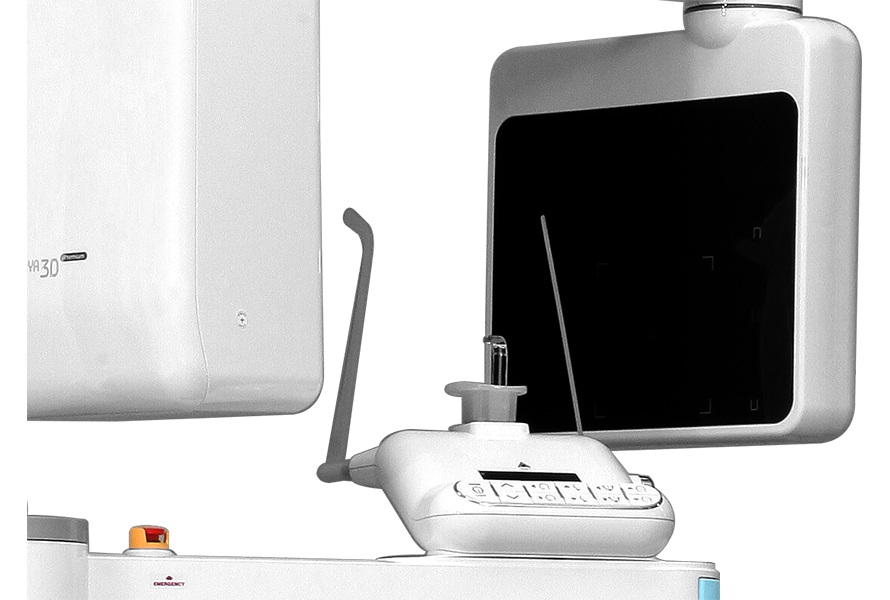

Удобный доступ

Обновленная и функциональная система позиционирования пациента для любых вариантов расположения аппарата.Обеспечивает удобство для всех пациентов и экономит ваше пространство.

Комфортное позиционирование

На нашем аппарате вы позиционируете пациента сидя, это помогает врачу свести к минимуму движения пациента при проведении исследования. А так же, является более комфортным методом выбора для детей и пожилых пациентовИнтеллектуальная система позиционирования